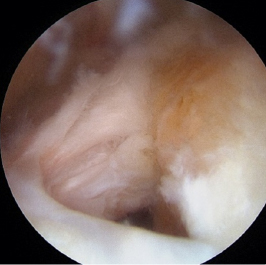

リバース型人工肩関節

肩腱板断裂

関節鏡下腱板修復術